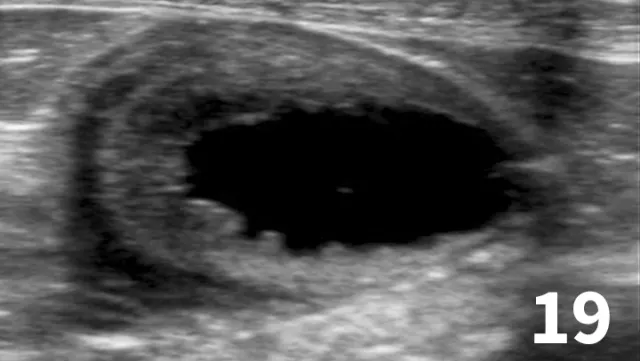

Survey radiographs of the urinary bladder are helpful for evaluation of size and location and for detection of radiopaque calculi. Urinary bladder distention is readily detected (Figure 17). Radiographs are of limited value in evaluating mural disease because the bladder wall cannot be differentiated from the fluid contained within the bladder. Bladder wall thickening (eg, bacterial inflammation, polypoid cystitis, neoplasia) is best evaluated by ultrasonography or double-contrast cystography (Figure 18). It should be noted that the degree of bladder filling can affect bladder wall thickness. For example, a small, mildly distended bladder may appear to have a thickened bladder wall on ultrasound compared with a moderately or severely distended bladder (Figure 19). This potential disadvantage can often be overcome by reevaluating the bladder several hours after preventing voiding.